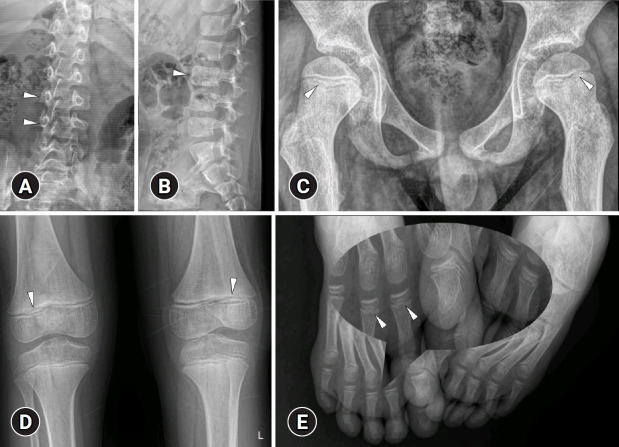

Spondyloenchondrodysplasia with immune dysregulation: an under-the-radar cause of spasticity.